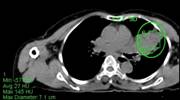

Ca lâm sàng 4: Bệnh nhân Lê V.T., nam, 73 tuổi. Chẩn đoán: U lympho ác tính không Hodgkin biểu hiện ở màng cứng ống tủy sống. Hình PET/CT cho thấy tổn thương tăng hấp thu FDG tại ống tuỷ sống